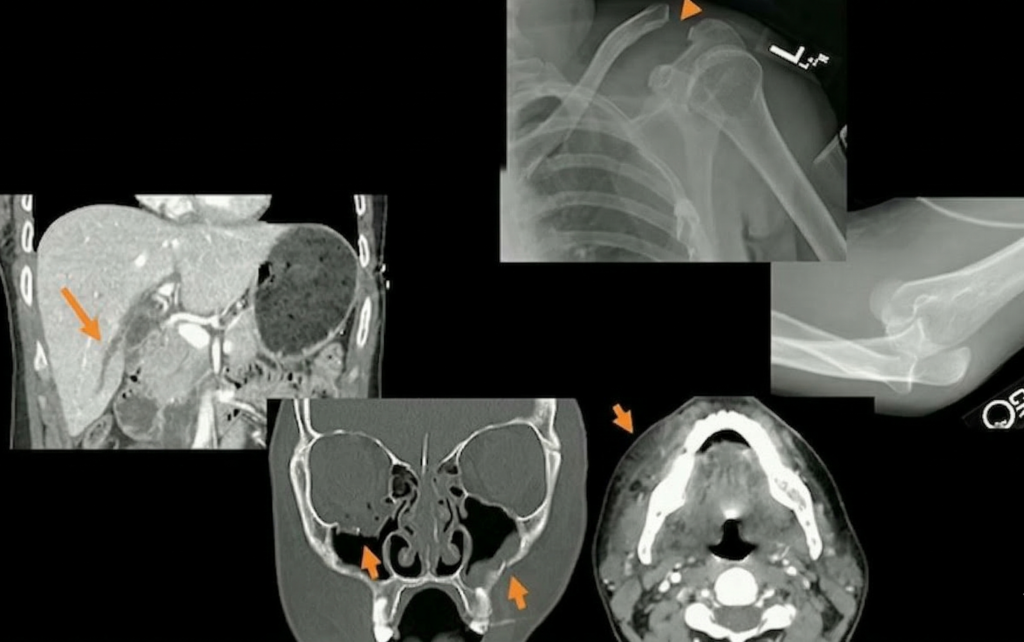

As Ellen X. Sun, MD, from the Trauma Imaging Research Innovation Center at Brigham and Women’s Hospital/Harvard Medical School outlined during the ARRS Web Lecture Emergency Radiology III, synchronous injuries in multiple locations without a history of major trauma are giant red flags. Common combinations include:

- Defensive Upper Extremity (UE) + Target Craniofacial Injuries

- Defensive UE + Target Abdominal Injuries

Dr. Sun presented a case study of a 24-year-old female patient who sustained both blunt and penetrating trauma from a partner she met on a dating app.

- Craniofacial: CT revealed multiple lacerations and facial fractures, including fracturing of the right orbital floor.

- Defensive: Radiography revealed a right-sided fifth middle phalangeal fracture, characteristic of defensive positioning.

Chronic Injuries: Injuries of different ages—such as the acute periorbital hematoma alongside a chronic nasal bone fracture below—are highly suspicious for repeated cycles of abuse.